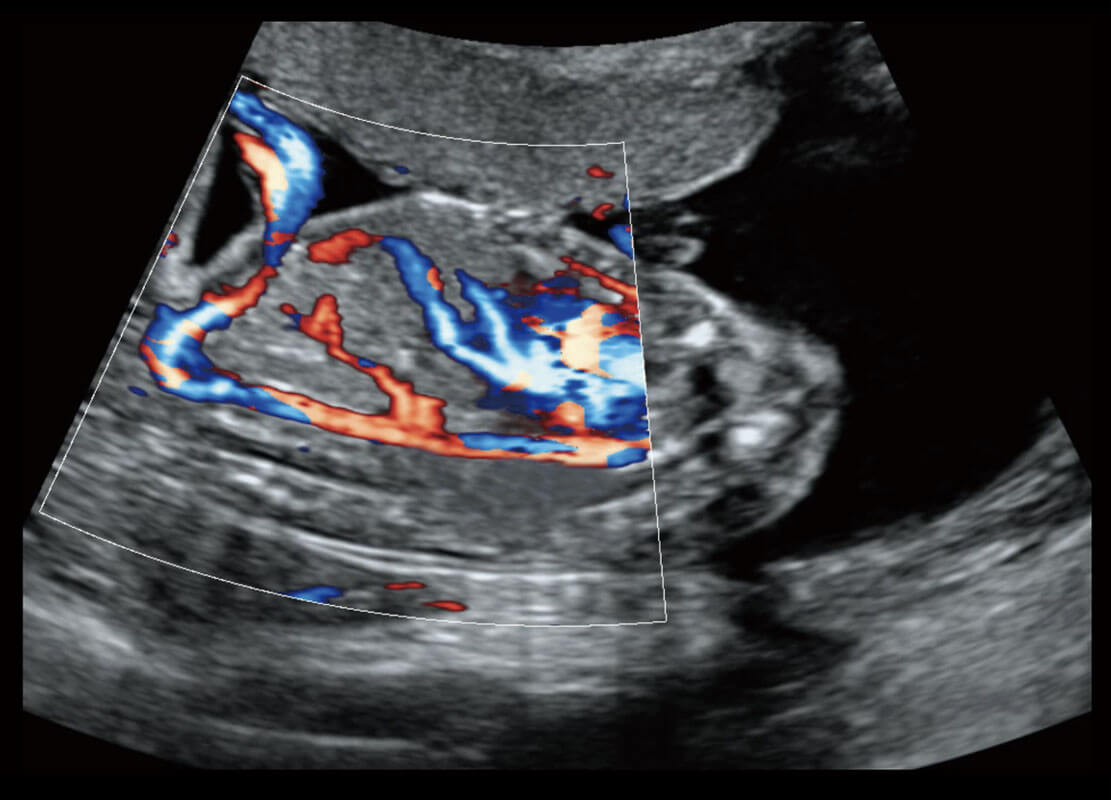

P60搭載寬頻帶線陣探頭、寬景成像、彈性成像技術(shù),為您提供乳腺應(yīng)用方案。P60支持高頻相控陣探頭、線陣探頭、腹部高頻探頭、腹部微凸探頭等,豐富的探頭群搭載敏感的彩色血流成像,適用于新生兒多種臟器檢測(cè)要求,滿足新生兒篩查需求。

乳腺癌顯微血流

新生兒肝血管癌